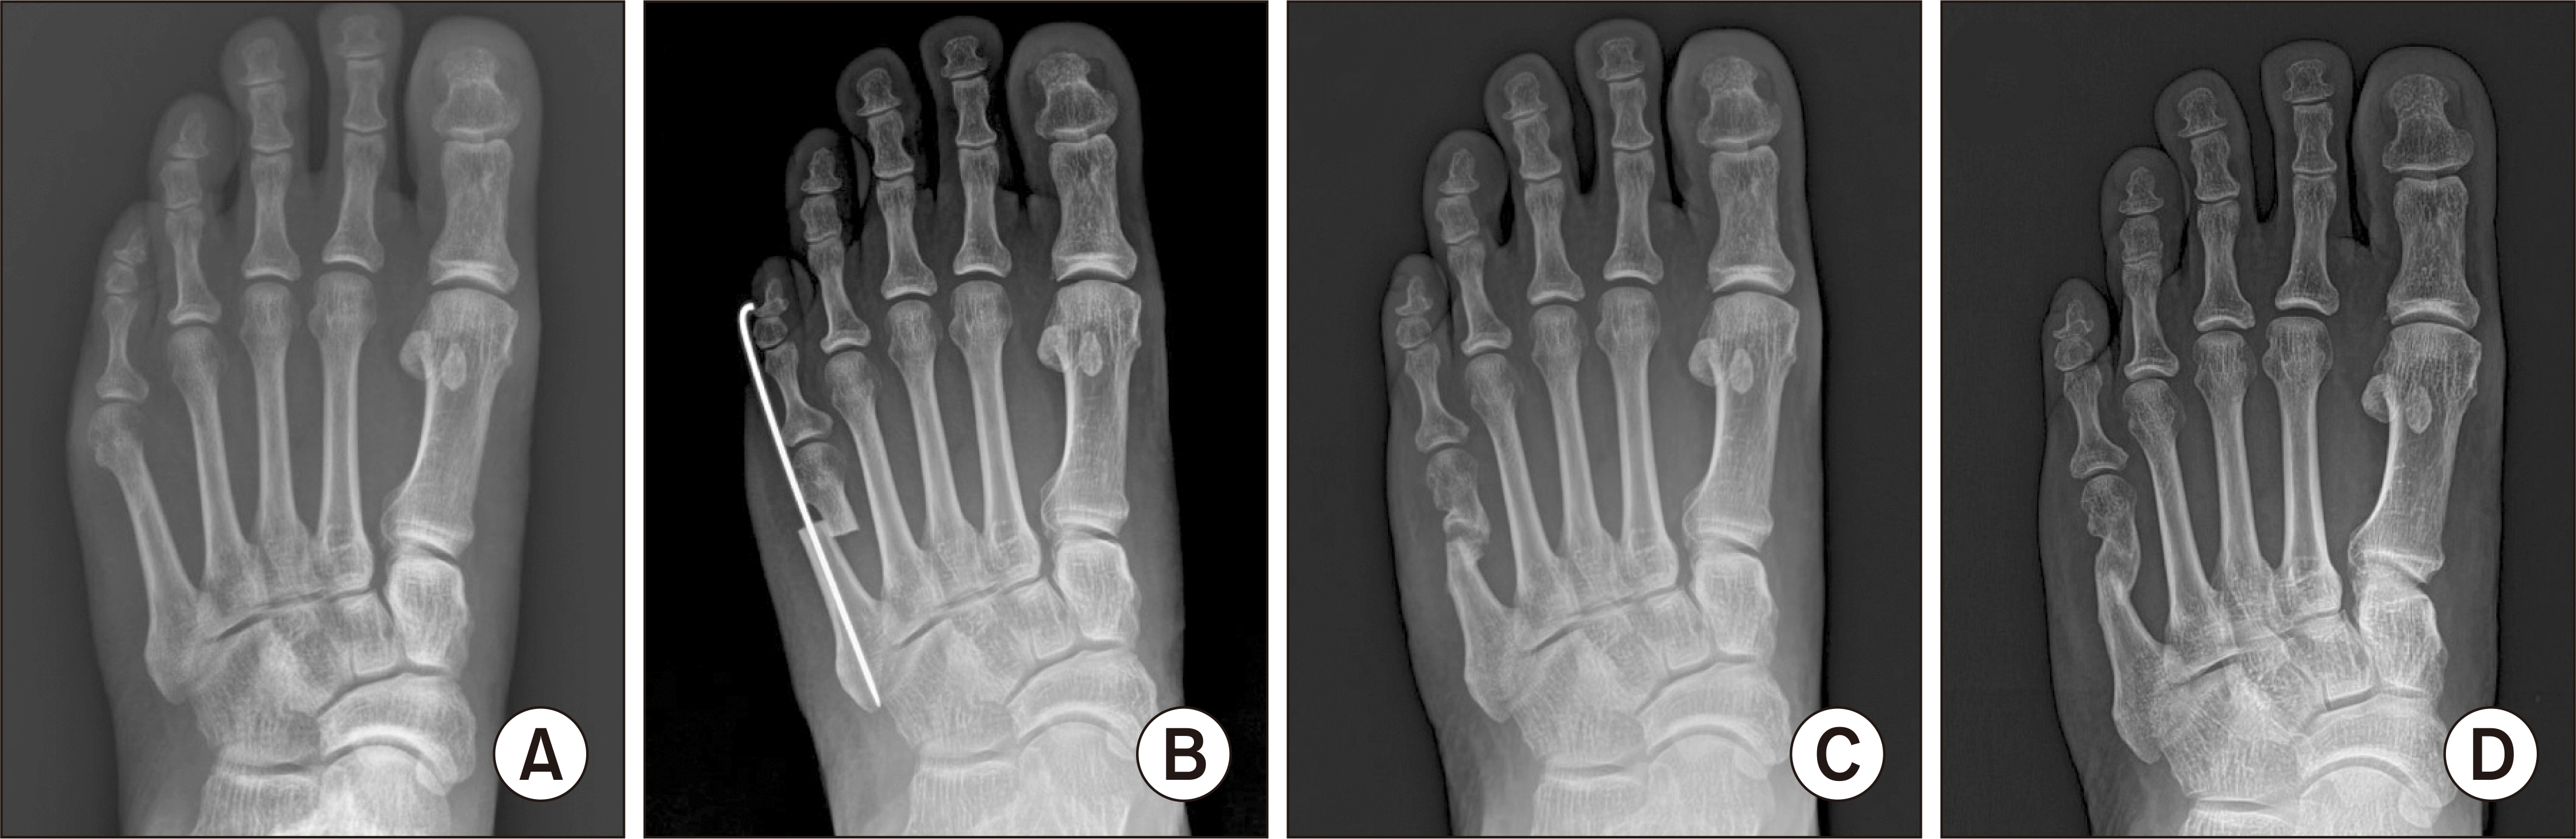

Radiographs of a 67-year-old male patient who has diabetic neuropathy with bunionette. Preoperative standing anteroposterior radiograph shows type III bunionette deformity by Fallat (A). S.E.R.I. operation was performed but radiograph shows metatarsal shortening due to over-correction (B). At postoperative 6 months, radiograph shows atrophic nonunion of the osteotomy site (C). But the bony union was achieved at the 12 months follow-up (D). S.E.R.I., simple, effective, rapid, inexpensive.

Table 1